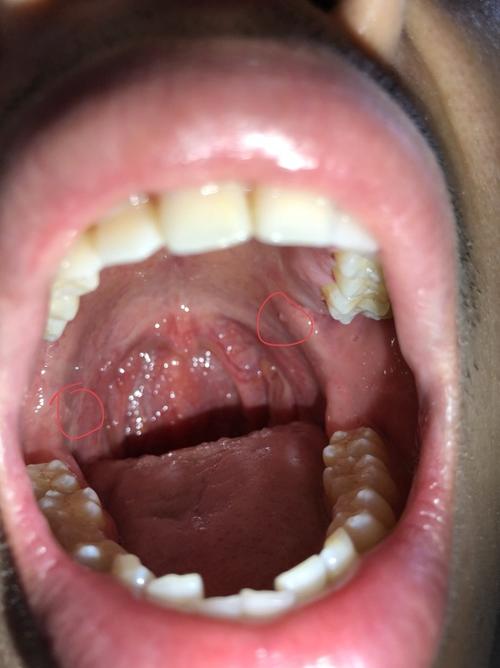

口腔内壁囊肿图片

口腔内壁囊肿图片,嘴巴内侧长肉疙瘩图片

口腔黏液囊肿

口腔内壁囊肿